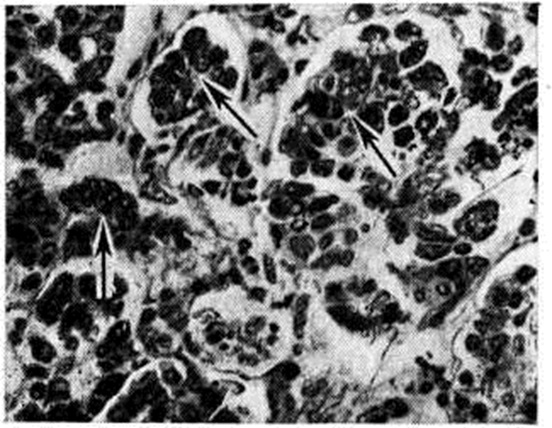

При микроскопическом исследовании костного мозга (смотри полный свод знаний) выявляется различная степень его опустошения. В случае аплазии в жировом костном мозге находят лишь небольшие скопления лимфоцитов, плазматических клеток и недифференцированных элементов, единичных гранулоцитов и нормобластов. При гипоплазии несколько чаще обнаруживают участки кроветворной ткани. Характерна неравномерность распространения очагов кроветворения не только в различных участках скелета, но и в пределах одной и той же кости. Структура костной ткани чаще сохранена. Как для ранних, так и для поздних фаз болезни характерно отложение гемосидерина в селезёнке, печени (рисунок 1) и костном мозге, реже в почках (рисунок 2), лимфатических, узлах. К частым осложнениям Гипопластическая анемия относят фибринозно-геморрагические пневмонии и некротические изменения в слизистых оболочках и серозных покровах, коже, внутренних органах. Течение и симптомы. Заболевание может протекать остро, подостро или хронически. В острых случаях процесс начинается с бурного геморрагического диатеза (смотри полный свод знаний Геморрагические диатезы), тяжёлой общей интоксикации, инфекционных осложнений. Чаще наблюдается постепенное нарастание симптомов. Появляются адинамия, слабость, головокружение, быстрая утомляемость, одышка при физ. нагрузке, иногда боли в костях и области сердца. Отмечается восковидная бледность кожи без желтушности, малокровие видимых слизистых оболочек. Подкожная жировая клетчатка сохранена. При развитии глубокой тромбоцитогонении (смотри полный свод знаний) возникают кровоизлияния на коже, слизистых оболочках и глазном дне, носовые, десневые, маточные, кишечные, почечные и другие кровотечения. При прогрессировании процесса может иметь место неврологический симптоматика, обусловленная геморрагиями в головной мозг. При парциальной Гипопластическая анемия кровоточивость отсутствует. Размеры лимф, узлов, селезёнки и печени не изменяются. Картина крови. Анемия носит нормохромный, нормоцитарный, реже макроцитарный характер. Полихроматофилия отсутствует, число ретикулоцитов нормально или снижено. Лейкопения может достигать 1000 клеток в 1 микролитров. и менее; она обусловлена в основном гранулоцитопенией и сопровождается относительным лимфоцитозом. Абсолютное число лимфоцитов при резкой лейкопении также снижено. Отмечается тромбоцитопения с удлинением времени кровотечения (смотри полный свод знаний) и снижением ретракции кровяного сгустка (смотри полный свод знаний Ретракция). Плазменные факторы свёртывания крови (смотри полный свод знаний Свёртывающая система крови) не изменяются. Содержание сывороточного железа повышено, общая железо-связывающая способность сыворотки чаще повышена. Парциальная Гипопластическая анемия характеризуется хронический нормоцитарной анемией, часто без лейко- и тромбоцитопении, с глубокой ретикулоцитопенией. Пунктат костного мозга, как правило, скудный, ядерные элементы представлены в основном лимфоцитами, немногочисленными гранулоцитами и нормобластами. Мегакариоциты чаще отсутствуют. Иногда, несмотря на явную панцитопению, пунктат оказывается довольно богатым; это связано с попаданием иглы в очаг сохранившегося кроветворения. Помимо чисто количественного дефицита эритробластических элементов, при Гипопластическая анемия отмечают признаки качественной их патологии (дизэритропоэз), мегалобластоидность, атипичные митозы, многоядерность (смотри полный свод знаний Дизэритропоэтическая анемия). При парциальной Гипопластическая анемия пунктат костного мозга богат ядерными элементами, лейкотромбоцитопоэз не нарушен, но число клеток красного ряда нередко резко уменьшено или они полностью отсутствуют. Трепанобиопсия подвздошной кости выявляет резкое преобладание жирового костного мозга над кроветворным (рисунок 3), иногда отсутствие последнего. Исследование с радиоактивным железом 59Fe даёт наиболее точную суммарную оценку эритропоэза: клиренс изотопа из плазмы замедлен, он накапливается в основном в печени, включение метки в эритроциты резко замедлено. Осложнения. Основными осложнениями и непосредственной причиной смерти больных являются кровотечения и инфекционно-воспалительные процессы. Геморрагии выявляются при снижении числа тромбоцитов ниже критического уровня (20 000—30 000 в 1 микролитров.), могут провоцироваться даже незначительными травмами (подкожные инъекции и так далее). Инфекции (пневмонии и другие) развиваются при достаточно длительном и выраженном (менее 500 в 1 микролитров.) снижении числа нейтрофилов. Всякая лихорадка у больных Гипопластическая анемия, как правило, связана с наличием инфекционного очага; описано немало случаев развития у них острого лейкоза. Лейкозы на фоне гипоплазии лучевого или бензольного происхождения относятся к группе миелобластных или миеломонобластных и являются, видимо, поздним результатом лейкемогенного действия фактора, вызвавшего анемию. Значительно реже наблюдается присоединение к Гипопластическая анемия пароксизмальной ночной гемоглобинурии, хотя некоторые авторы трактуют в этих случаях Гипопластическая анемия как гипопластическую стадию данной формы гемолитической анемии. Диагноз основывается на наличии панцитопении и бедного ядерными клетками пунктата или трепаната костного мозга при отсутствии увеличения лимф, узлов, селезёнки и печени. Гипопластическая анемия следует дифференцировать главным образом с панцитопениями другого происхождения. Обнаружение в крови молодых клеток белого или красного ряда, даже незначительное увеличение селезёнки всегда должны вызывать сомнение в диагнозе Гипопластическая анемия. В этих случаях можно предположить наличие алейкемических форм лейкозов (смотри полный свод знаний), раковых метастазов в костный мозг, миеломной болезни (смотри полный свод знаний). Диагноз обычно ставят на основании исследования пунктата костного мозга; миеломной болезни, кроме того, присущи характерные изменения белков сыворотки и (или) мочи. Панцитопения при миелофиброзе (смотри полный свод знаний Остеомиелофиброз) сопровождается, в отличие от Гипопластическая анемия, увеличением и миелоидной метаплазией селезёнки. Анемию Аддисона — Бирмера (смотри полный свод знаний Пернициозная анемия) отличает от Гипопластическая анемия наличие глоссита, неврологический нарушений, ахлоргидрии, выраженного мегалобластоза костного мозга, хорошего терапевтического эффекта от витамина В12. Диагноз пароксизмальной ночной гемоглобинурии даже в её ранней, гипопластической, стадии подтверждается положительными результатами сахарозной и кислотной проб (смотри полный свод знаний Гемолитическая анемия). При подостром варианте лимфогранулематоза (смотри полный свод знаний) панцитопения сопровождается лихорадкой, нет резкого лимфоцитоза, в трепанате костного мозга иногда удаётся обнаружить клетки Березовского — Штернберга. Панцитопения вследствие гиперспленизма сопровождается, как правило, увеличением селезёнки. ЛечениеМетодов радикального излечения Гипопластическая анемия не существует, однако лечебный мероприятия способствуют удлинению продолжительности жизни больных. При выявлении этиологического фактора необходимо прекратить дальнейшее его воздействие. Для борьбы с анемией показаны трансфузии крови или эритроцитарной массы; эта мера не должна преследовать цель полной нормализации показателей красной крови — достаточно поддержание их на уровне, совместимом с сердечно-сосудистой компенсацией. Число трансфузий должно быть минимальным для уменьшения опасности трансфузионного сидероза (при переливании 450 миллилитров крови в организм вводится 200—250 миллиграмм железа), гепатита и других осложнений. Во избежание изосенсибилизации антигенами лейкоцитов и тромбоцитов целесообразно переливать отмытые эритроциты. При многократных гемотрансфузиях нередко развитие изосенсибилизации антигенами эритроцитов; в этих случаях кровь для трансфузии подбирают по непрямой пробе Кумбса (смотри полный свод знаний Кумбса реакция). В случае сочетания анемии с геморрагическим диатезом показаны переливания свежецитратной крови или прямые гемотрансфузии в разовой дозе не менее 500 миллилитров. Более выраженным гемостатическим эффектом обладают тромбоцитарные концентраты, получаемые с помощью сепаратора клеток крови от одного донора или путём центрифугирования большого числа доз крови, взятых от различных доноров. Кровоостанавливающее действие тромбоконцентратов проявляется в том случае, если число тромбоцитов у больного удаётся повысить хотя бы до 15 000 —20 000 в 1 микролитров. крови. При многократных переливаниях тромбоцитарных концентратов, особенно полученных из крови разных доноров, неизбежно развивается изосенсибилизация к тромбоцитарным антигенам и отмечается снижение терапевтической эффективности трансфузий. Поэтому желательно в качестве доноров использовать ограниченное число лиц, лучше родственников, максимально совместимых по антигенам системы HL — А (смотри полный свод знаний Группы крови, лейкоцитарные антигены). Среди лекарственных препаратов свойством стимулировать эритропоэз обладают лишь анаболические стероиды (смотри полный свод знаний). Необходимым условием достижения терапевтического эффекта считают длительность применения гормонов в достаточно высокой дозе (например, метилтестостерон или неробол по 1 — 2 миллиграмм на 1 килограмм веса тела в день внутрь в течение 3—4 месяцев) [Мак-Креди (К. В. Mc-Credie), 1969]. Первым проявлением лечебный эффективности препаратов может быть улучшение показателей периферической крови. При появлении признаков побочного действия (задержка жидкости, поражение печени) гормоны отменяют. Для лечения Гипопластическая анемия применяют также кортикостероиды (преднизолон 0,5—1,0 миллиграмм на 1 килограмм веса тела или эквивалентные дозы других стероидов) главным образом с целью гемостатического действия (понижение сосудистой проницаемости); для этого используют и другие, так называемый сосудоукрепляющие средства — аскорбиновую кислоту, рутин, препараты кальция. С целью уменьшения гемосидероза органов и тканей можно назначать препараты типа десферала. Многочисленные попытки пересадки больным донорского костного мозга, предпринимавшиеся без должного иммунологический подбора (только по основным эритроцитарным антигенам), оказались безуспешными, то есть завершились отторжением трансплантата вследствие биол. несовместимости. Случаи подлинной трансплантации немногочисленны. Томас (Е. D. Thomas) с сотрудники (1974) осуществили у четырёх больных Гипопластическая анемия успешную пересадку сингенного костного мозга, полученного от однояйцевых близнецов больных, приведшую к полному выздоровлению; операция проводилась без специальной подготовки ввиду антигенной идентичности реципиентов и доноров. Однако подобная возможность является казуистической. Аллогенные пересадки (от доноров, совместимых по системе Н1—А) требуют сложной подготовки реципиентов для предотвращения отторжения трансплантата (общее облучение или введение циклофосфана с целью иммунодепрессии), а также послеоперационного применения цитостатиков для подавления иммунологический реакции «трансплантат против хозяина» (смотри полный свод знаний Несовместимость иммунологическая). Из 24 больных Гипопластическая анемия, описанных Томасом с сотрудники, 12 прожили свыше 3 месяцев; приживление у них трансплантата было доказано в результате анализа полового хроматина (смотри полный свод знаний). У больных, получивших ранее многочисленные гемотрансфузии, шансы на приживление трансплантата в связи с образованием изоантител снижаются. Сложность методики пересадки костного мозга делает ее доступной лишь для отдельных специализированных учреждений. Вопрос об эффективности спленэктомии окончательно не решён. При выраженных геморрагиях операция противопоказана в связи с высокой летальностью. Вероятно, более целесообразна спленэктомия (смотри полный свод знаний) у больных с повышенной секвестрацией тромбоцитов и эритроцитов в селезёнке, доказанной радиоизотопным методом, и при сохранности очагов нормального кроветворения в костном мозге. ПрогнозПрогностически неблагоприятным признаком считают острое начало болезни. Формы с острым течением обычно устойчивы к терапии и через несколько недель заканчиваются смертью. Чаще течение болезни затяжное, многомесячное и даже многолетнее. Возможно длительное отсутствие клин, проявлений заболевания, однако у больных сохраняются признаки неполноценного костномозгового кроветворения. ПрофилактикаЛица, профессионально связанные с воздействием миелотоксических факторов (источники ионизирующей радиации, бензольное производство), должны находиться под постоянным диспансерным наблюдением. Проведение цитостатического лечения по поводу опухолей и других заболеваний требует регулярного контроля состава крови и своевременного прекращения при угрозе гипоплазии кроветворения. Применение потенциально опасных препаратов, в первую очередь левомицетина (смотри полный свод знаний), должно быть ограничено прямыми показаниями и находиться под контролем состава крови. Профилактика геморрагий при уже развившейся Гипопластическая анемия включает гормональное подавление менструального цикла у женщин с массивными меноррагиями, замену (по возможности) инъекционных лечебный препаратов пероральными, щажение слизистых оболочек (исключение грубой пищи, замена жёстких зубных щёток ватными тампонами). Для предотвращения инфекционных осложнений при глубокой гранулоцитопении (смотри полный свод знаний Лейкопения) рекомендуется подавление кишечной аутофлоры неабсорбируемыми антибиотиками, больных следует содержать в асептических или близких к ним условиях, следить за соблюдением личной гигиены. Гипопластическая анемия у детей. Приобретённые формы Гипопластическая анемия у детей протекают так же, как у взрослых. Наряду с ними в детском возрасте встречаются и некоторые врождённые (конституциональные) формы болезни. Анемия Фанкони (синонимы: синдром Фанкони, врождённая панцитопения). Описана в 1927 год под названием «семейная детская пернициозоподобная анемия». С тех пор опубликовано около 200 наблюдений. Анемия, как правило, выявляется в первые годы жизни, изредка позже. Мальчики болеют в 2 раза чаще девочек. Характерно сочетание панцитопении и гипоплазии костного мозга с другими врождёнными дефектами — коричневой пигментацией кожи в связи с отложением меланина, атрофией почек и селезёнки, отсутствием или недоразвитием 1 пястной или лучевой костей, задержкой умственного, физ. и полового развития, микроцефалией, микроофтальмией. При культивировании лимфоцитов и фибробластов кожи больных выявляются многочисленные хромосомные аберрации. У родственников больных часто отмечают лейкозы. Лечение — назначают систематические переливания крови (эритроцитарной массы). Прогноз неблагоприятный. Семейная гипопластическая анемия Эстрена — Дамешека впервые была описана в 1947 год. Ей свойственны те же изменения со стороны кроветворения, которые наблюдаются при анемии Фанкони, но аномалий развития скелета и внутренних органов не наблюдается. Врождённая парциальная гипопластическая анемия Джозефса — Даймонда — Блекфена описана в 1936 год Джозефсом (W. Н. Josephs) и в 1938 год Даймондом и Блекфеном (L. К. Diamond, К. D. Blackfan). Генетический дефект, лежащий в основе болезни, не выяснен. Развитие болезни у нескольких детей, родившихся от разных матерей, но от одного отца, свидетельствует о доминантном характере наследования. Развёрнутая картина болезни обычно обнаруживается уже на 1-м году жизни: анемия различной степени сочетается с глубокой эритро- и нормобластопенией на фоне уменьшения количества миелокариоцитов (на начальных этапах развития болезни количество миелокариоцитов костного мозга может быть не изменено). У части больных выявляют другие врождённые дефекты (задержка полового и физических развития), но аномалии развития почек не встречаются. Вследствие многократных гемотрансфузий нередко развивается гемосидероз с портальным циррозом печени (смотри полный свод знаний Циррозы печени). Лечение — систематические переливания крови (эритроцитарной массы) в сочетании с кортикостероидными гормонами и витамином В12. При помощи систематических гемотрансфузий удавалось довести больных детей до 8—15 лет, после чего наступало спонтанное улучшение. Смотри также Анемия.